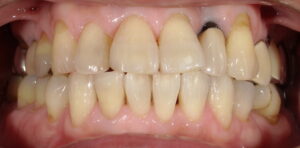

術後:完全ではありませんが、だいぶ白くなりました。

料金:¥33,000(税込み)

治療回数:2回